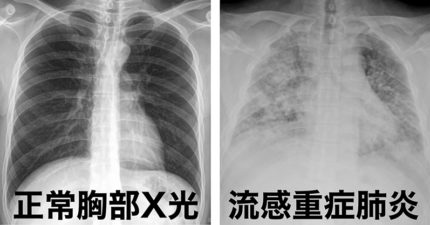

怎麼肺炎人就走了?胸腔醫示警6症狀快送醫「死亡率高達40%」